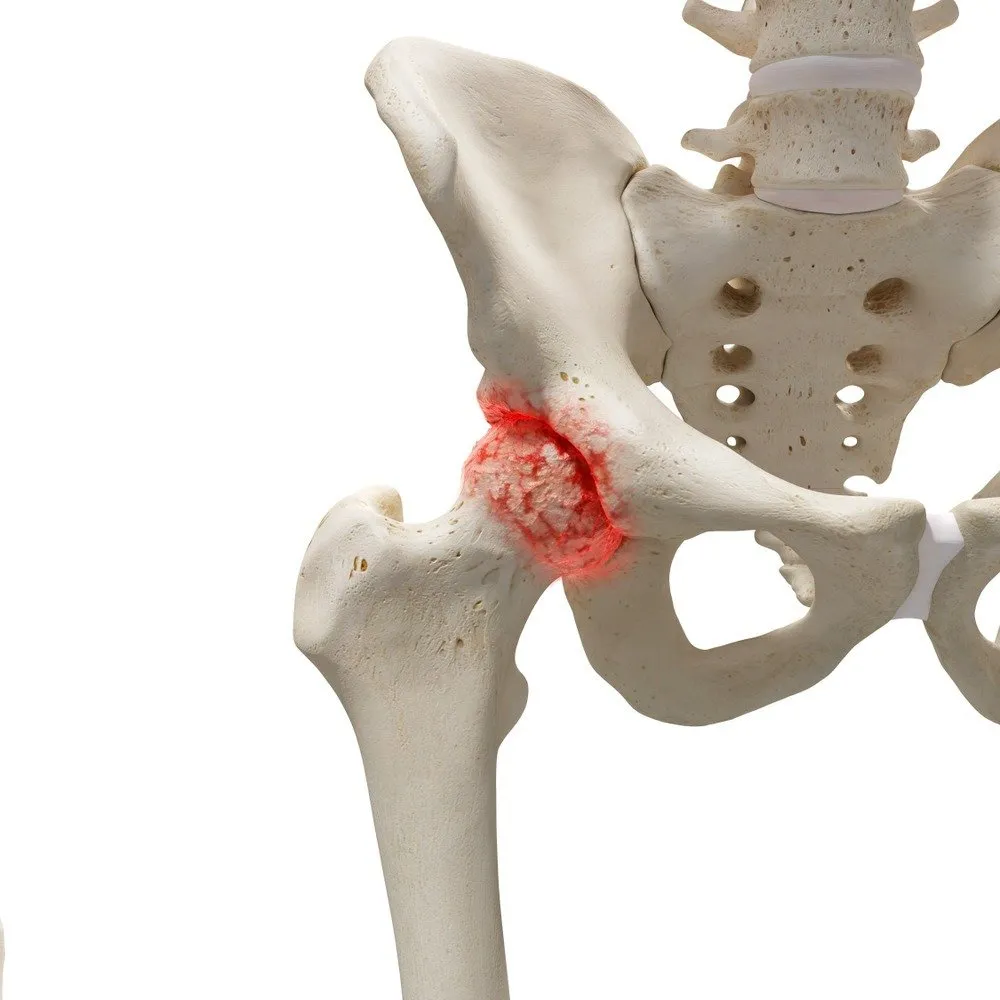

고관절 질환 3. 대퇴골두 무혈성 괴사증

소켓 모양의 고관절에 맞물리는 둥근 모양의 대퇴골두가 혈액 순환 문제로 뼈 조직이 괴사하는 질환이며, 대퇴골두 무혈성 괴사가 주요 원인입니다. 주로 30~50대에 나타나며, 남성의 발병률이 여성보다 높습니다. 약 60%가 양측성으로 나타나고, 주된 원인은 기저 질환으로 인한 코르티코스테로이드의 장기 사용과 과도한 알코올 섭취로, 전체 사례의 약 90%를 차지합니다.

괴사의 크기가 작고 통증이 일상생활에 큰 영향을 주지 않는 초기에는 약물 치료와 경과 관찰을 통해 관리하는 것이 좋습니다.

질환이 더 진행될 경우, 감압 수술은 괴사 부위의 압력을 낮추고 정상적인 혈액 공급을 회복하는 데 효과적입니다. 관절 치환술은 나이에 관계없이 괴사 부위가 넓거나 초기 단계라도 심한 통증을 겪는 노인 환자에게 특히 유용합니다.